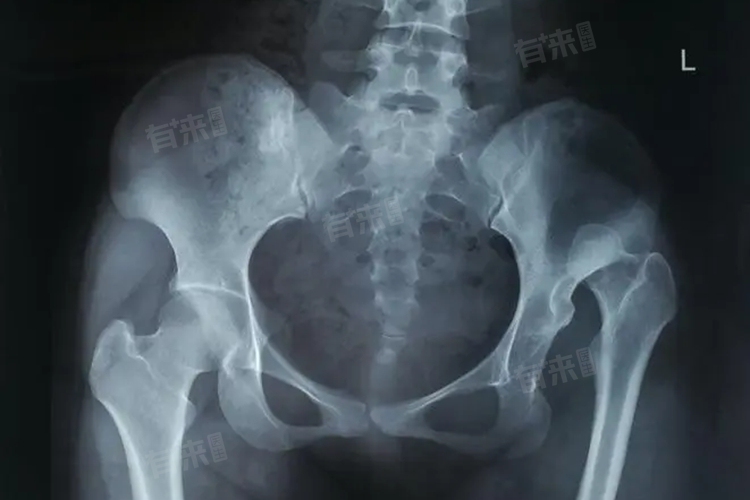

2、先天性因素:先天性髋关节发育不良或脱位是婴幼儿时期常见的原因,患者在出生时即表现出髋关节的异常,如髋关节脱位或发育不良,从而导致胯骨一边高一边低的现象,通过拍摄X光片可以明确诊断。

3、股骨头坏死:可能导致胯骨不对称的疾病,当一侧股骨头发生坏死并塌陷时,该侧肢体会出现短缩,进而表现为胯骨一边高一边低,患者还可能伴有髋关节疼痛和活动受限等症状。